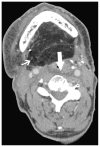

Cross-sectional imaging plays an important role in the evaluation of the retropharyngeal space (RPS) and the prevertebral space (PVS). Because of their deep location within the neck, lesions arising within these spaces are difficult, if not impossible, to evaluate on clinical examination. This article details the cross-sectional anatomy and imaging appearances of primary and secondary diseases involving the RPS and PVS, including metastasis and spread from adjacent spaces. The role of image-guided biopsy is also discussed.